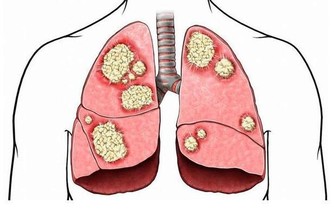

三、便秘慢病患者

如果慢病患者有便秘,請抓緊治療。因為排便不暢,會導致患者在排便時非常用力,

如果患者心臟不太好,或者由動脈粥樣硬化斑塊,突然用力很可能導致心臟血流驟然提高,

很可能誘發心臟斑塊脫落,誘發大面積心梗,最終引起猝死。